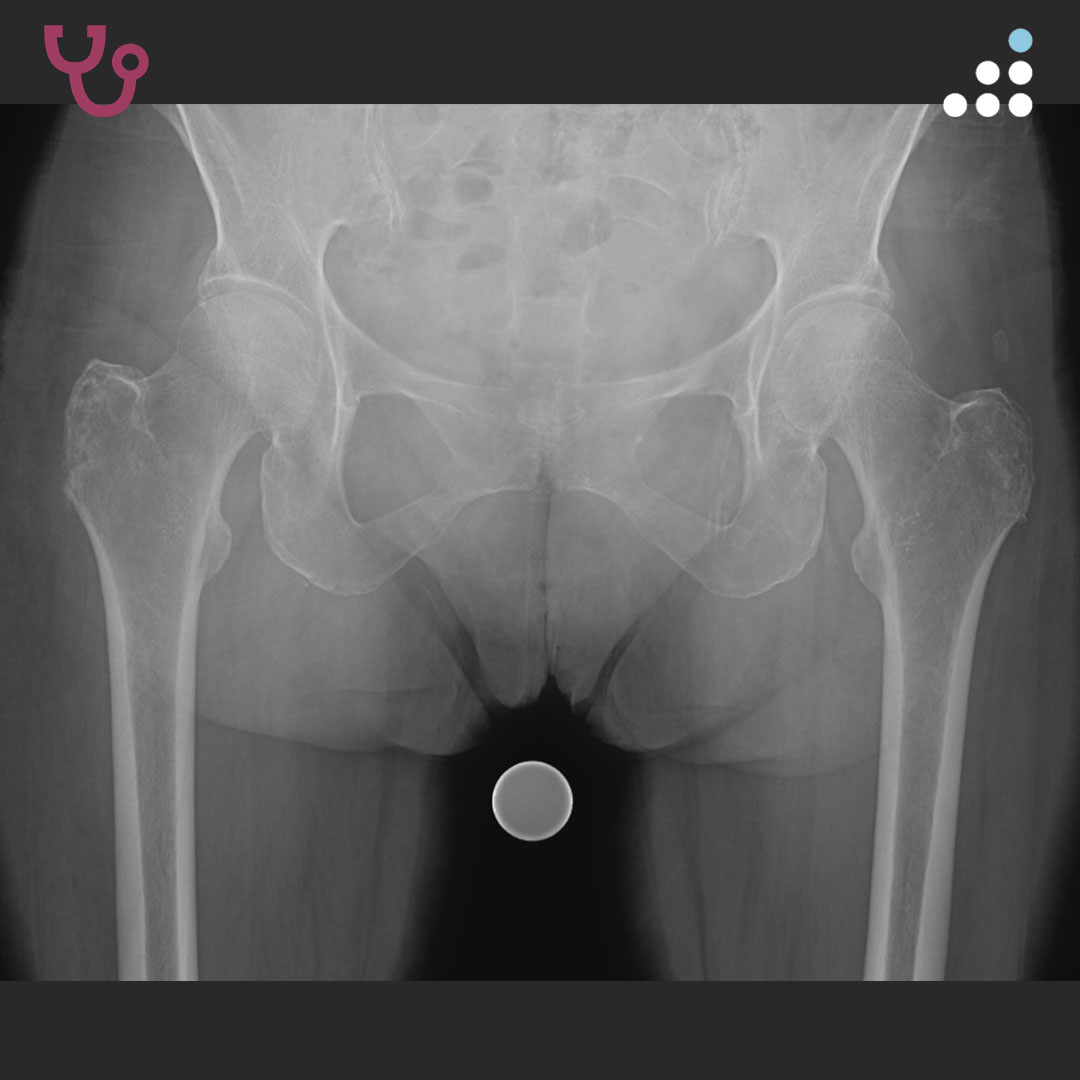

DYSPLASTIC HIP IN 20M WITH CEREBRAL PALSY